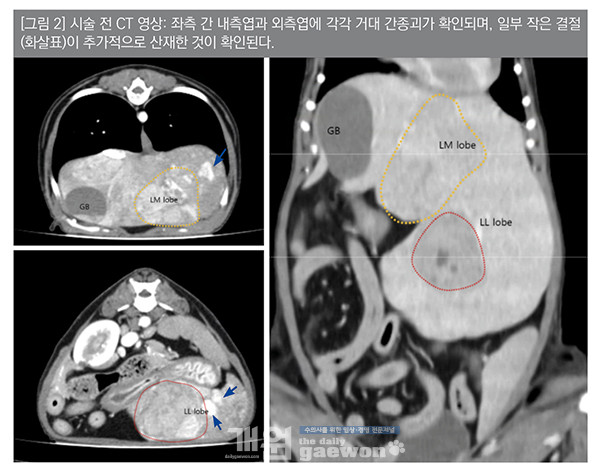

14살의 중성화 수컷 요크셔테리어 환자가 건강검진상 간수치 증가가 확인되었다. 복부초음파 및 CT 검사 결과,간 좌측 내측엽과 외측엽에 각각 거대 종괴가 확인 되었으며,그 외 작은 결절들도 추가적으로 확인되었다[그림 2].

세침흡인검사에서 간 종괴는 간세포암종(HCC)이 의심되는 악성도가 높은 간세포가 탈락되었다. 환자는 간 좌측 내측엽과 외측엽 모두 종괴가 존재하여수술적 교정을 할 경우 간 좌측 내측엽과 외측엽을 모두 제거해야 하는데,술 후 남은 간기능이 저하될 수 있으며, 14살의 노령견으로 수술 중 사망 위험성 및 술 후 합병증 가능성 또한 높게 판단 되었다.